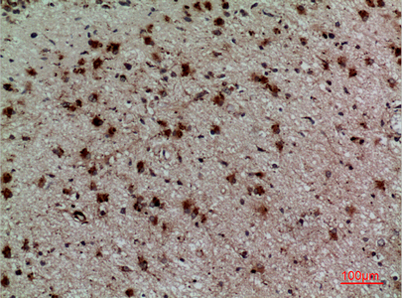

Product name: CD158z rabbit pAb

Dilutions: Western Blot: 1/500 - 1/2000. IHC-p: 1:100-300 ELISA: 1/20000. Not yet tested in other applications.

Immunogen: The antiserum was produced against synthesized peptide derived from the Internal region of human KIR3DL3. AA range:231-280